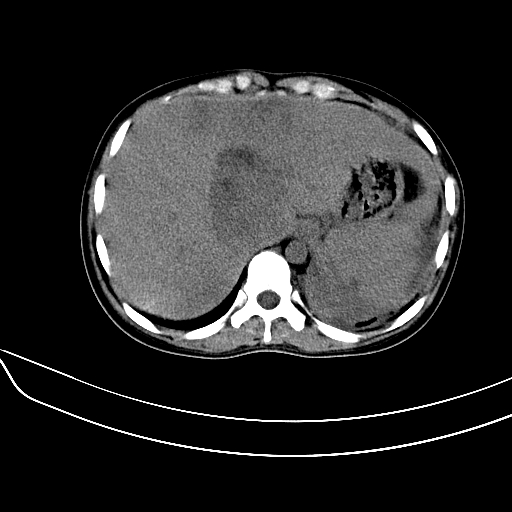

标题: CT7307:糖尿病引起的肝、脾损害?

女,22岁,临床以糖尿病等病史入院,两年前有妊娠合并胰腺炎史,现有多饮、多尿、咳嗽、咳痰、左腰痛、发热等。因多种原因没做增强。

考虑1:肝脏肿瘤并脾脏转移;

2:左腹膜后肿瘤;

3:脾脏梗塞不排除;

4:少量腹水。

考虑1: 糖尿病并发 肝脏脾脏梗塞不排除;少量腹水

脾梗塞,包膜下慢性血肿。肝脏低密度病灶不好说,脂肪肝算是一种可能。

肝、脾增大,内见多发低密度影,少量腹水,左侧肾周筋膜增厚,结合病人糖尿病史,有左腰痛、发热,考虑:糖尿病激发肝脾病变(梗塞?),左侧肾周感染,建议进一步检查。